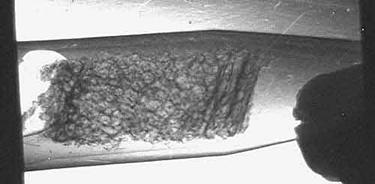

На Курчатовском источнике СИ были проведены исследования биоптатов костной ткани человека, предоставленные Центральным институтом травматологии и ортопедии им.Н.Н.Приорова (ЦИТО). Биоптаты представляют собой небольшие фрагменты, объемом менее одного кубического сантиметра, извлеченные посредством операции из кости и помещенные в формалин. На рис.5 показаны снимки, сделанные методом рефракции (а) и поглощения (б). Видно, что структура кости на рис.5,а проявляется значительно лучше, чем на рисунке 5,б. На верхнем рисунке хорошо виден внешний (кортикальный слой) кости, а также внутренний, который состоит из продольных слоев (трабекул) размером до нескольких сотен микрон. Здесь использование синхротронного излучения приобретает особое значение, потому что другие методы для оценки прочности кости оказываются малоприменимыми. Хотя с помощью электронного микроскопа, дающего очень высокое пространственное разрешение, можно увидеть в кости кристаллы кальцита размером около 1 мкм, но в практической медицине это пока не нашло широкого применения. На синхротронных пучках размеры и ориентацию таких кристаллов удается определять с помощью электронной спектроскопии.

Рис. 5. Изображение биоптата кости человека, полученное методом рефракции (а) и поглощения (б) на Курчатовском источнике СИ.